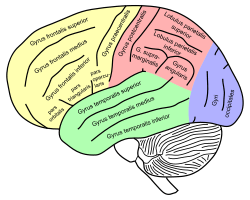

Sensory homunculus of the human brain. Lateral view of a human brain, main gyri labeled.

Lateral view of a human brain, main gyri labeled.